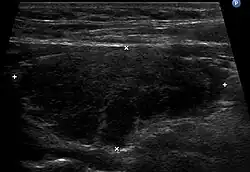

Échographie thyroïdienne en coupe longitudinale montrant un lobe thyroïdien augmenté de volume, hypoéchogène et hétérogène dans le cadre d'une thyroïdite de Hashimoto.

L'échographie de la thyroïde montre un goitre hypoéchogène[20],[18]. Le parenchyme thyroïdien devient plus hétérogène au cours de l'évolution. On peut notamment mettre en évidence des pseudo-nodules et des nodules de régénérations hyperéchogènes (white knight)[18]. Des ganglions récurrentiels peuvent être visualisés[18]. La vascularisation est hétérogène en Doppler couleur. L'étude en Doppler pulsé retrouve une élévation des vitesses systoliques[18], toutefois moindre que dans la maladie de Basedow.